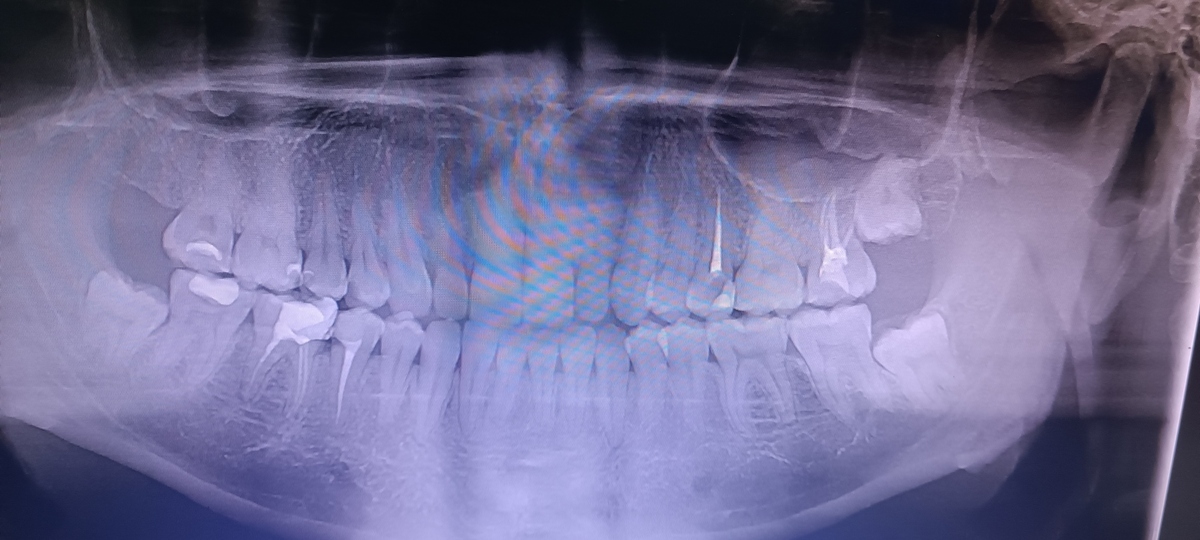

Шея зуб